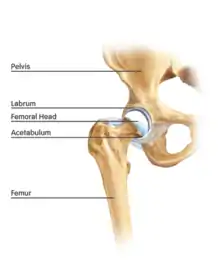

The hip is essentially a ball and socket joint. It consists of the head of the femur (the ball) and the acetabulum (the socket). Both the ball and socket are congruous and covered with hyaline (or articular) cartilage, which allows smooth, almost frictionless gliding between the two surfaces. The edge of the acetabulum is surrounded by the acetabular labrum, a fibrous structure that envelops the femoral head. (See fig. 1) The labrum acts as a seal, or gasket, around the femoral head. However, this is not its only function, as it has been shown to contain nerve endings, which may cause pain if damaged.[18] The blood supply of the labrum has also been demonstrated.[25] The joint itself is encompassed by a thick, fibrous joint capsule, which is lined by synovium. The ligaments that keep the hip joint in place are in fact, thickened areas of joint capsule, rather than distinct structures. The synovium generates fluid that lubricates the joint; in that fluid are the nutrients needed to keep the cartilage cells alive. A total of 27 muscles cross the hip joint, making it a very deep part of the body for arthroscopic access. This is one reason why hip arthroscopy can be quite technically demanding.

Labral tears

The acetabular labrum is a fibrous structure, which surrounds the femoral head. It forms a seal to the hip joint,[15] although its true function is poorly understood. Recent evidence has demonstrated that this hydraulic seal is vital for maintaining stability of the ball and socket joint [16] and reducing contact pressures of the femur to the acetabulum.[17] The labrum has also been shown to have a nerve supply and as such may cause pain if damaged.[18] The underside of the labrum is continuous with the acetabular articular cartilage so any compressive forces that affect the labrum may also cause articular cartilage damage, particularly at the junction between the two, the chondrolabral junction. The labrum may be damaged or torn as part of an underlying process, such as FAI or dysplasia (shallow hip socket), or may be injured directly by a traumatic event. Depending on the type of tear, the labrum may be either trimmed (debrided) or repaired. Removing or debriding the labrum is becoming less popular as the latest research shows that results are more predictable in the long term if the labrum can be repaired. Various techniques are available for labral repair, mainly using anchors, which may be used to re-stabilise the labrum against the underlying bone, allowing it to heal in position.